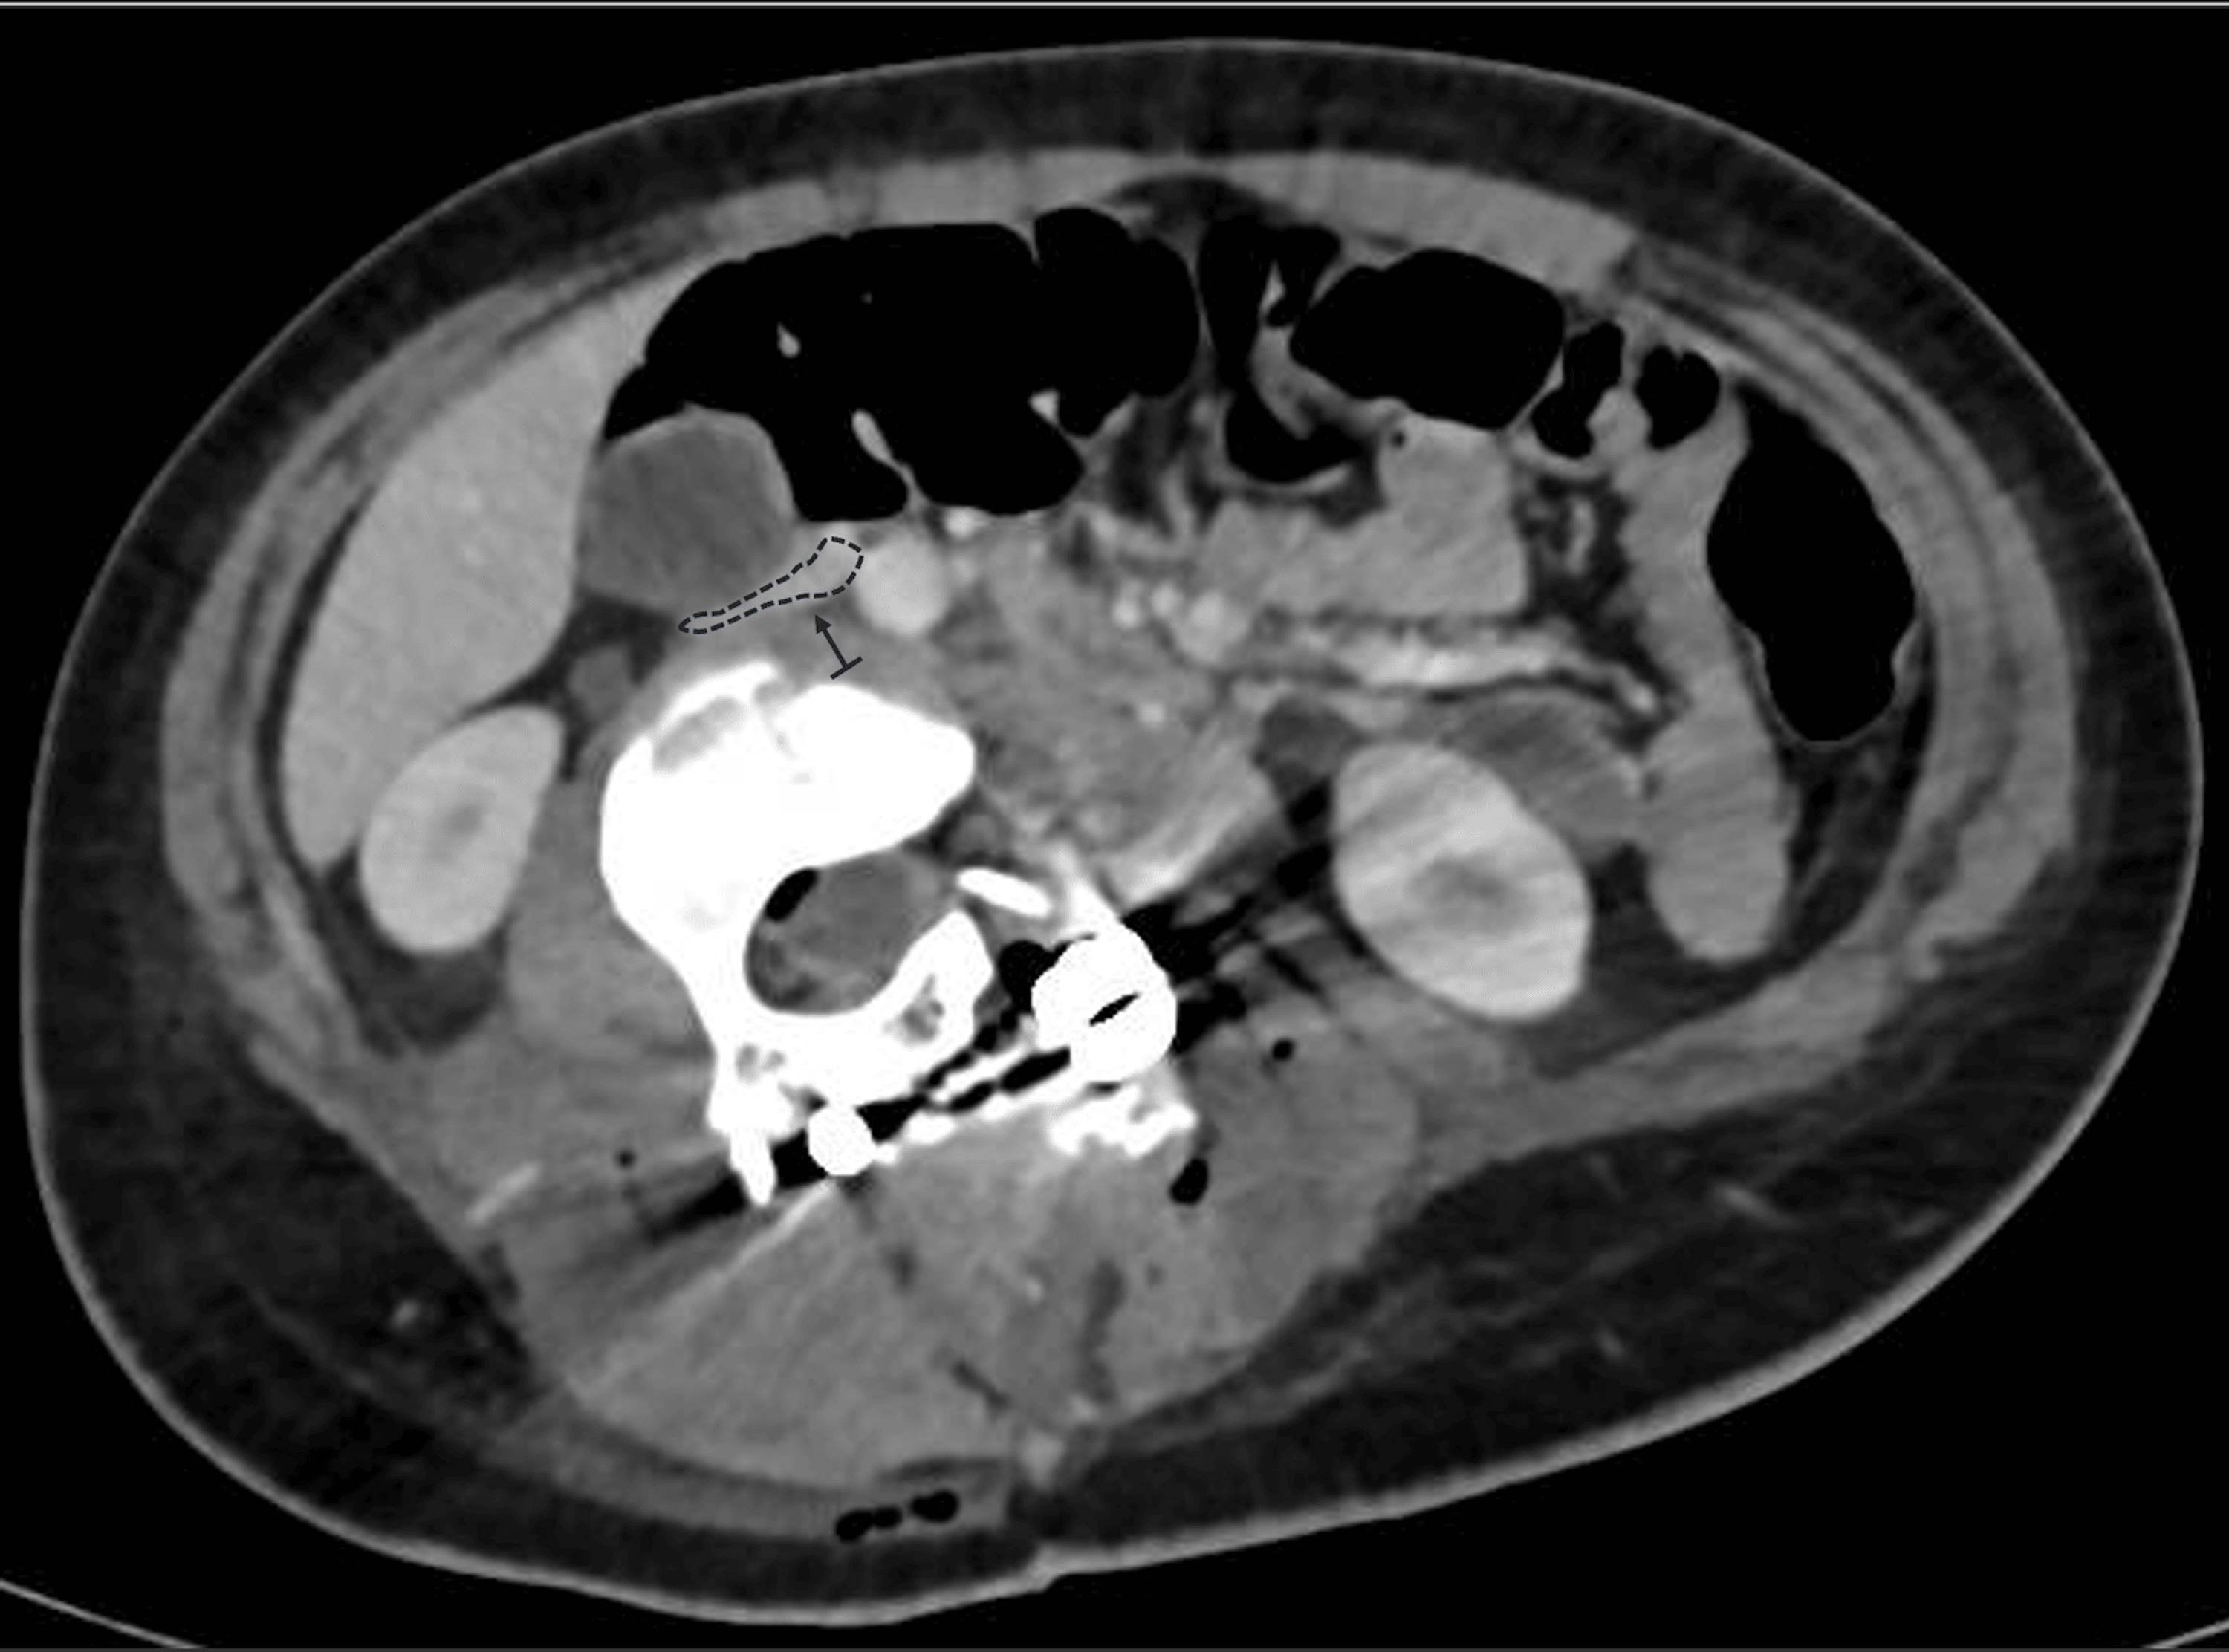

Radiographs demonstrated a 67° lumbar scoliosis due to an L3 hemivertebra fused ventrally and dorsally with L4. Previous imaging showed progression from 22° at age eight to 54° at age 11. Preoperative laboratory tests were within normal limits, including hemoglobin of 13.6 g/dL (reference range: 12.0-14.0 g/dL) and hematocrit of 40% (reference range: 36-43%). Preoperative traction radiographs demonstrated partial curve correction to 37° (Figure 1a). A computed tomography (CT) evaluation confirmed the previously described characteristics, including a 67° lumbar scoliosis caused by a ventral and dorsal fusion of L3 and L4 vertebrae. Additionally, the preoperative CT scan revealed that the IVC and aorta were located within the concavity of the spinal curve, a finding commonly observed in scoliosis cases. No other abnormalities were detected in other organs.

The patient remained hemodynamically stable postoperatively but exhibited persistent sinus tachycardia. Laboratory tests revealed a drop in hemoglobin to 9.2 g/dL (reference range: 12.0-14.0 g/dL) and an elevation in lactate to 11.6 (reference range: 6.3-18.9 mg/dL) mg/dL. She received a transfusion of 460 mL of packed red blood cells, which improved her hemoglobin to 12 g/dL. Postoperative CT angiography demonstrated substantial compression and displacement of the IVC, resulting in a 60% reduction in its lumen diameter at the L3 level (Figure 2). No evidence of thrombus or venous return obstruction was found. Furthermore, cardiology evaluation and echocardiography were performed to rule out other differential diagnoses that might explain the intraoperative hemodynamic changes, thereby excluding cardiac abnormalities. Furthermore, it was determined not to administer anticoagulation to the patient, despite the IVC compression, based on the absence of venous stasis or thrombotic findings on imaging. This conservative approach aligns with previous recommendations suggesting targeted intervention only when hemodynamic or thrombotic complications are evident [2,4].

In severe scoliosis, the anatomical positions of the great vessels are markedly altered, with the IVC and aorta frequently residing within the concavity of the spinal curve. This displacement effectively shortens their vascular length relative to a neutral alignment. Thus, during surgical maneuvers that involve rotation or lengthening of the spinal column, the anterior structures are exposed to significant tension and compression forces. In our case, where the hemivertebra was fused with adjacent vertebrae, forming a substantial mass similar to a vertebral block, it is plausible that derotation, by increasing lumbar lordosis and facilitating the anterior translation of the apical block vertebrae, reduced the distance between the spine and the anterior abdominal wall. Moreover, this derotation may have contributed to spinal elongation and stretching of the anterior soft tissues. These mechanisms are supported by postoperative CT angiography, which demonstrated that the correction maneuver increased the anterior spinal length, exerting significant traction on the IVC and reducing its lumen diameter by approximately 50% at the L3 level. Similar findings have been reported in studies examining vascular shifts during scoliosis correction, indicating that the position and diameter of the IVC and aorta are highly dependent on the severity and rigidity of the deformity [1,4].

Accurate preoperative imaging is essential for identifying potential risks in severe and rigid scoliosis surgery. Advanced imaging techniques such as CT angiography can map the spatial relationship between the spine and adjacent vascular structures, providing critical insights into the risk of compression or elongation during correction [4,11]. In this case, postoperative imaging confirmed significant compression and displacement of the IVC into the concavity of the deformity. While the absence of thrombus or obstruction at rest was reassuring, this finding emphasized the dynamic nature of vascular compression during surgical manipulation. Dynamic imaging modalities, such as upright CT or MRI, could offer additional information by simulating positional changes and their impact on venous return [4].